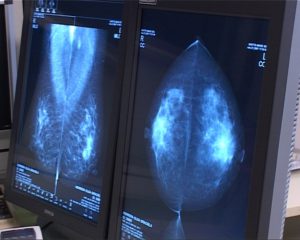

Bellunesi in testa alle classifiche regionali per quanto riguarda gli screening oncologici. In molti casi superata la quota dell’80%[videojs poster=’https://static1-telebelluno.fra1.cdn.digitaloceanspaces.com/wp-content/uploads/2017/01/16noni_011417A6PREVENZIONE.jpg’ mp4=’https://static1-telebelluno.fra1.cdn.digitaloceanspaces.com/wp-content/uploads/2017/01/16noni_011417A6PREVENZIONE.mp4′ ogg=’https://static1-telebelluno.fra1.cdn.digitaloceanspaces.com/wp-content/uploads/2017/01/16noni_011417A6PREVENZIONE.ogg’][/videojs]